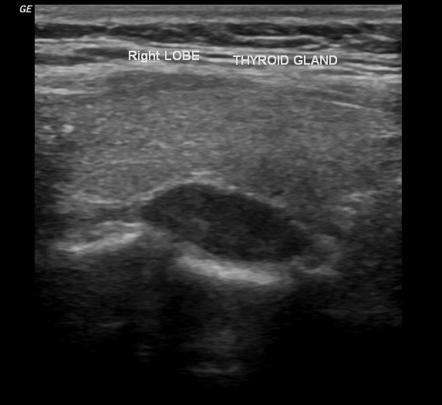

Ультразвуковое исследование при подозрении на опухоль паращитовидных желез проводится в рамках эндокринологического обследования шеи с использованием серошкального В-режима и цветовой допплерографии. Цель исследования — выявление прямых анатомических признаков опухолевого образования, его локализации, формы, эхогенности, васкуляризации и степени компрессии прилежащих структур.

Ультразвуковое исследование выявляет следующие анатомические признаки опухоли паращитовидных желез:

Аденома паращитовидной железы:

Чётко отграниченное гипоэхогенное образование овальной или округлой формы с равномерным снижением эхогенности относительно ткани щитовидной железы.

Расположение кзади или книзу от соответствующей доли щитовидной железы, чаще одностороннее.

Гомогенная внутренняя эхоструктура без кальцинатов с возможными небольшими анэхогенными включениями.

Выраженная внутритканевая васкуляризация по данным цветового допплеровского картирования с преобладанием сосудов по периферии и в питающем сосудистом пучке.

Чёткая капсула, визуализируемая как гиперэхогенный ободок по периферии образования.